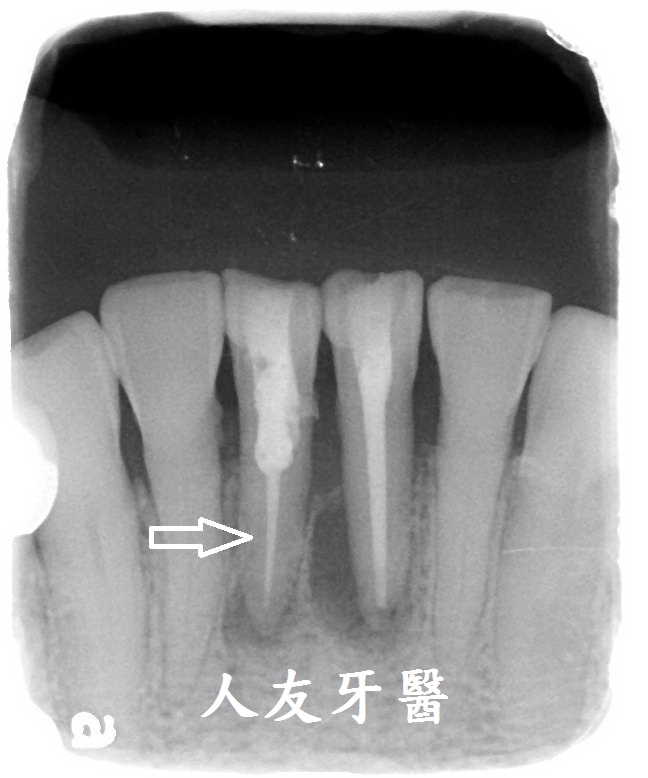

患者因牙齦萎縮牙根裸露有蛀牙覺得不適 , 牙套上的瓷粉又剝落 , 患者在醫師的建議下將舊的牙橋拆掉 , 蛀牙重新填補後再做不含金屬的數位電腦3D掃描設計全鋯牙橋 .